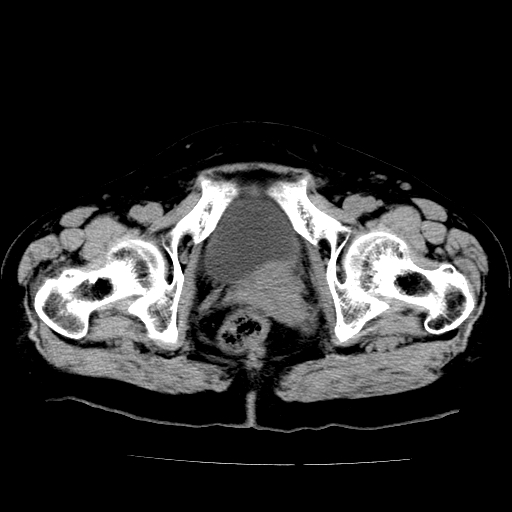

女,73岁,阴道流血一周。

宫颈不规则增大;结合临床考虑宫颈癌。建议作mri检查

1\\老年妇女突发阴道流血,常见病考虑宫颈癌.本病例宫颈部显示形态不规则,密度欠均匀,支持考虑宫 颈癌,建议mri 或阴道超声坚持

2\\但是盆腔两侧尚未见到明显肿大淋巴结等转移征象

宫颈不规则增大,左后方可见结节状突起.支持宫颈癌.

宫颈壁明显增厚,左侧为甚,宫颈癌待排,建议宫颈涂片细胞学检查。

宫颈不规则增大,周围脂肪间隙毛糙,结合临床考虑宫颈癌,盆腔内未见肿大淋巴结。